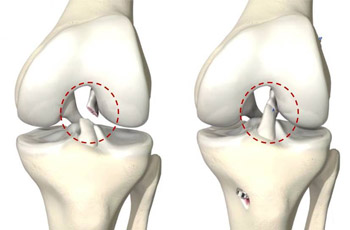

KNOW MOREA tear in the ACL ligament can cause major injury in the knee and you need to consult the best ACL doctor in Jaipur. The knee joint is formed by the three bony structures called the femur, the tibia, and the patella. The Anterior Cruciate Ligament (ACL) is known to be the main ligaments in the knee that connect the femur to the tibia and is one of the commonly injured ligaments of the knee.